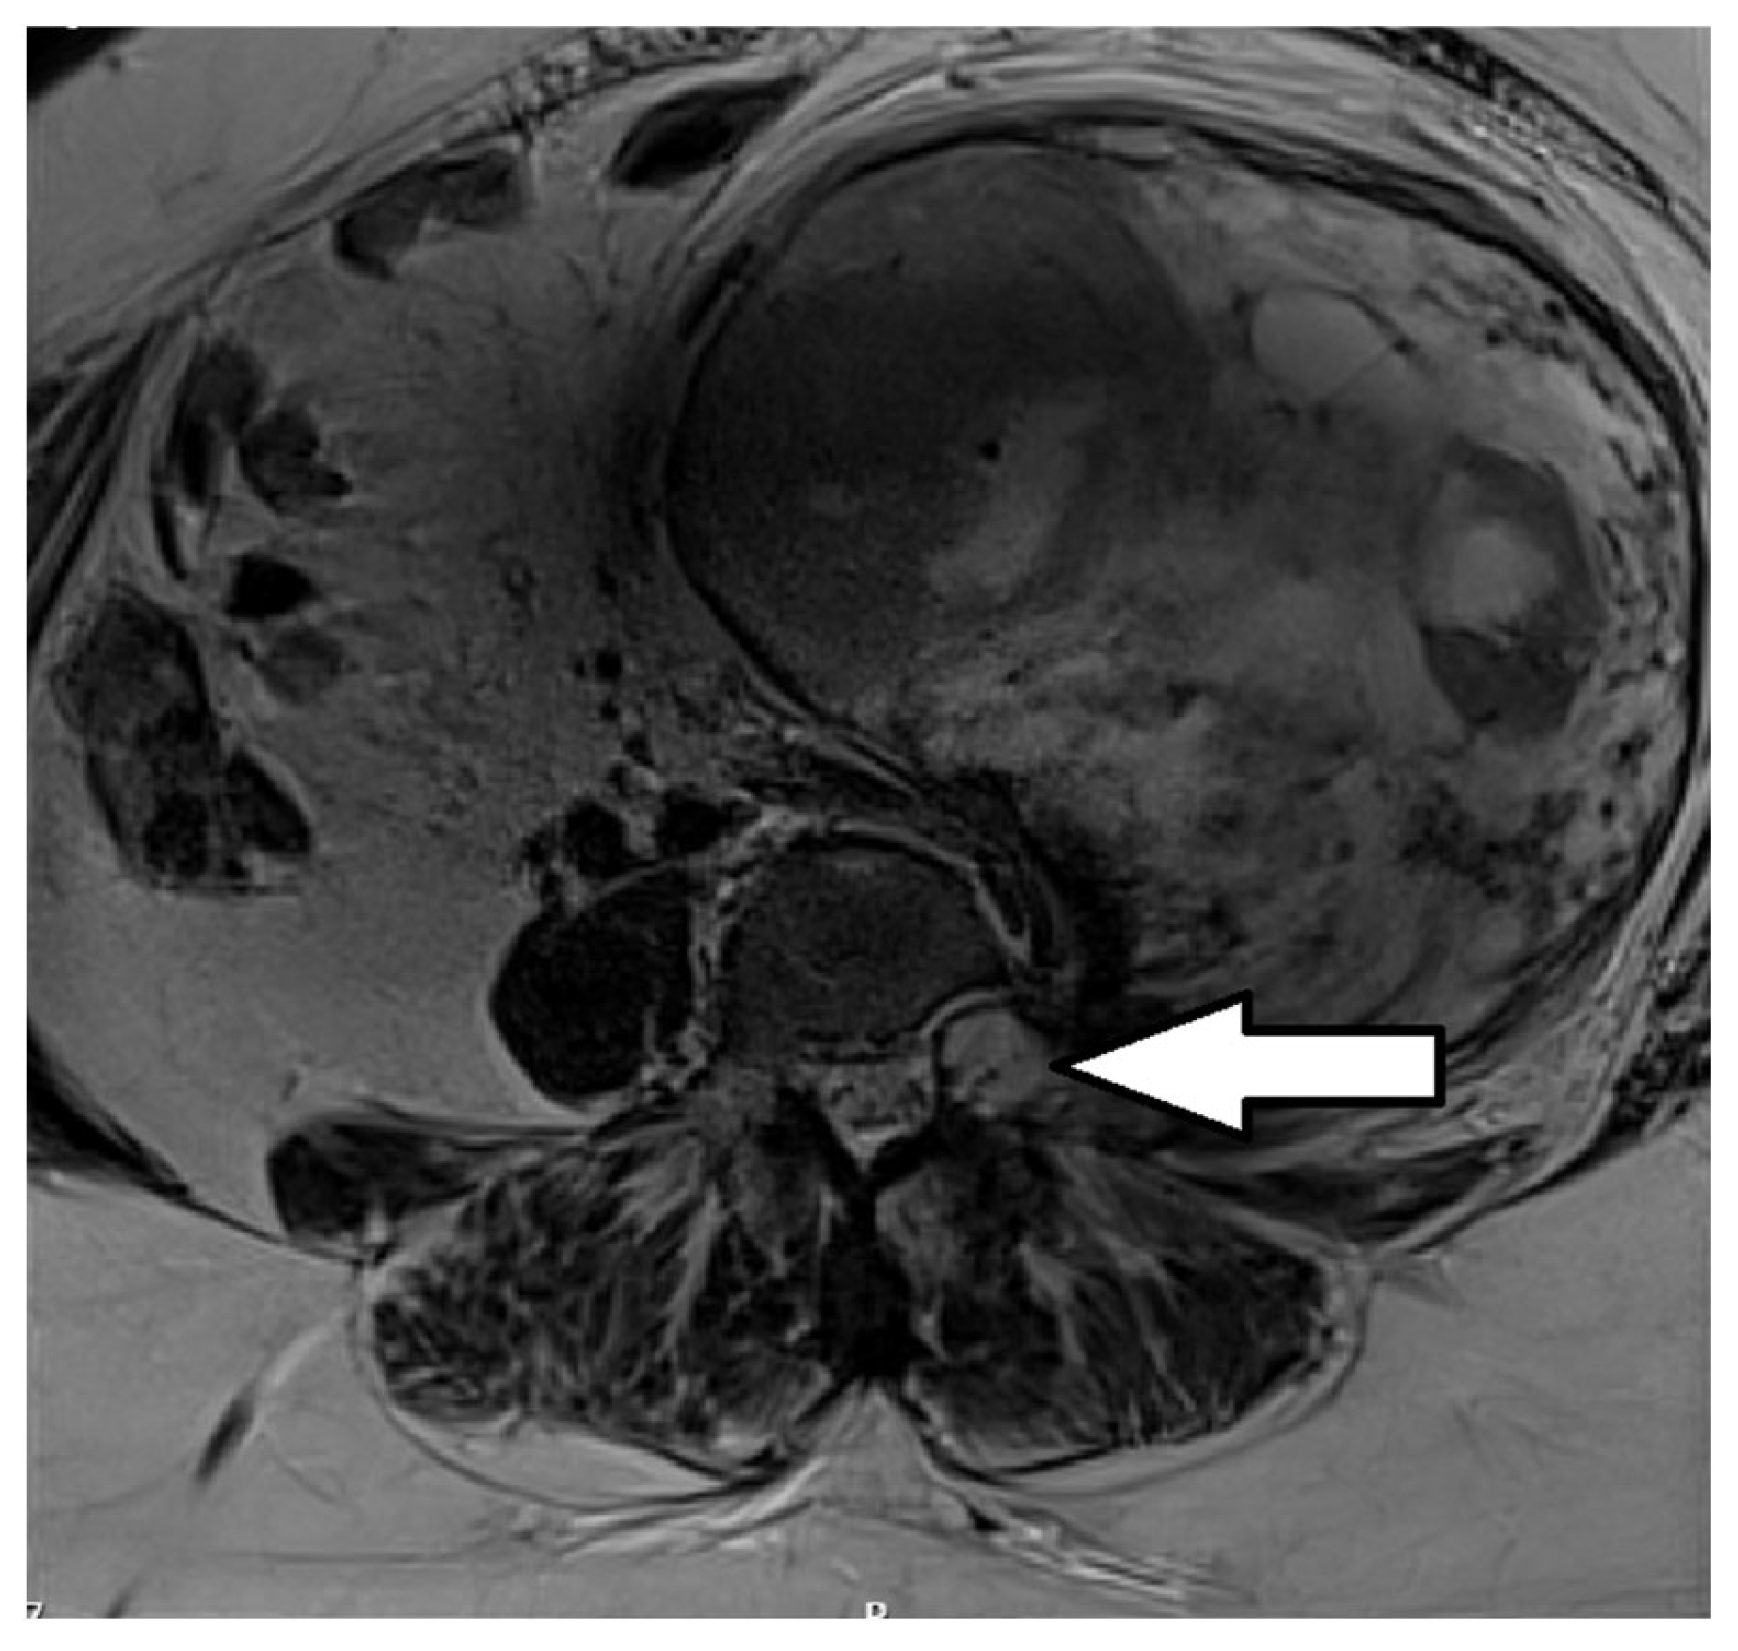

2. Case Report